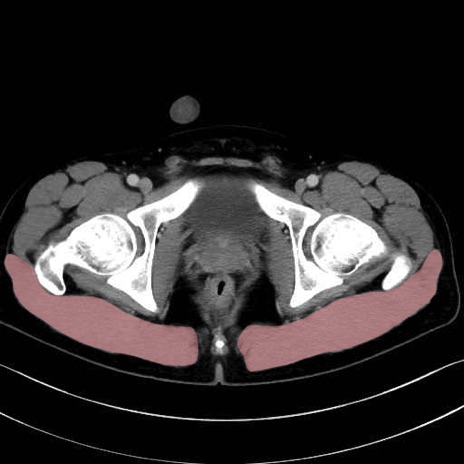

大殿筋 (Gluteus maximus)